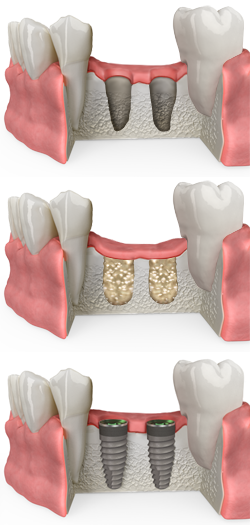

Missing teeth can lead to a number of problems, including bone loss in your jaw. This bone loss can make it difficult to replace missing teeth with dental implants, a permanent and natural-looking solution. At Dental Elements, your trusted dentist in Downtown Denver, we offer dental bone grafting to restore bone volume and create a strong foundation for successful dental implants.

Dental bone grafting is a surgical procedure used to rebuild lost bone in the jaw. This bone can be taken from another location in your own body (autograft), donated by a tissue bank (allograft), or derived from synthetic materials. The grafted bone is then placed in the area where bone has been lost and allowed to heal. Once healed, the bone provides a stable base for the placement of dental implants.